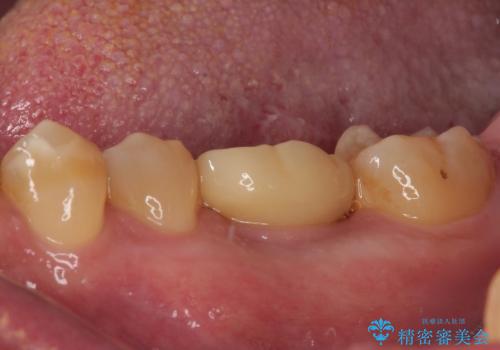

咬合力で破折した奥歯 抜歯即時埋入インプラントによる補綴治療

インプラント埋入時に植立具合の安定性を測定したところ、十分な数値が得られたため、速やかに仮歯を装着して咬合回復をさせることができました。

抜歯を含めた外科処置を1回に抑えることができ、あっという間に治療を終えることができました。